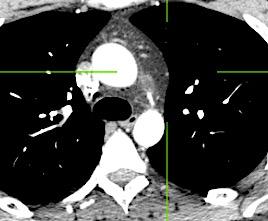

Diafragma “colgante” (“dangling sign”)

(“Dangling sign”)

TC. Mejor con multicorte. (reconstrucciones).

Asociación: Aire en pared.

Fracturas costal .Rotura esplénica. Neumoperitoneo.

Diafragma discontinúo Herniación de la grasa omental

Desser TS et al.The dangling diaphragm sign: sensitivity and comparison with existing CT signs of blunt traumatic diaphragmatic rupture. Emerg Radiol 2010